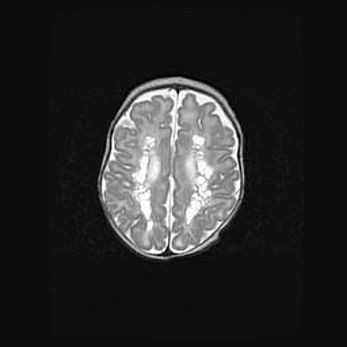

Открытая гидроцефалия.

Возраст: 9 месяцев 12 дней

Вес: 6800 г

Пол: мужской

Окружность головы: 41,5 см

Срок гестации: 28 недель

Гидроцефалия головного мозга у новорожденных имеет характерный признак: опережающий рост окружности головы приводит к визуально хорошо определяемой гидроцефальной форме сильно увеличенного в объёме черепа. Детские неврологи определяют следующие симптомы гидроцефалии у грудничков: выбухающий напряжённый родничок, частое запрокидывание головы, смещение глазных яблок к низу.